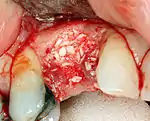

An incision is made across the area and the flap of gingiva is opened to show the bone of the jaw.

An incision is made across the gingiva, and the flap of tissue is reflected to show the bone of the jaw.